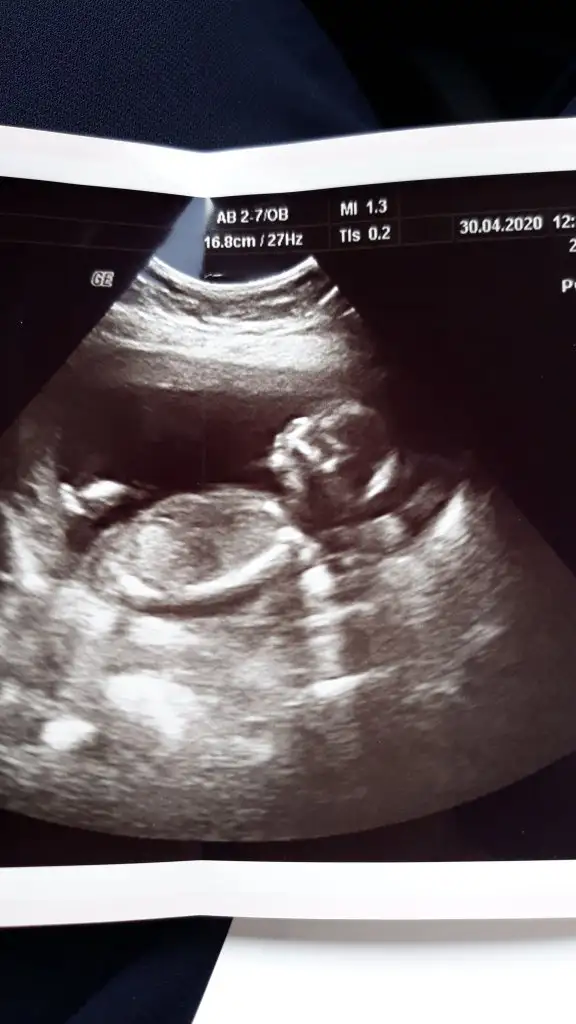

Evet paralele yakın açıda kız oldugunu düşünüyorumHayırlı bayramlar![]()

Ikra meyra başka bir açıdan daha resim atıcam o bacak arası kısmında görülen net beyaz çizgi nub mu oluyor

Çok teşekkür ederimEvet paralele yakın açıda kız oldugunu düşünüyorum